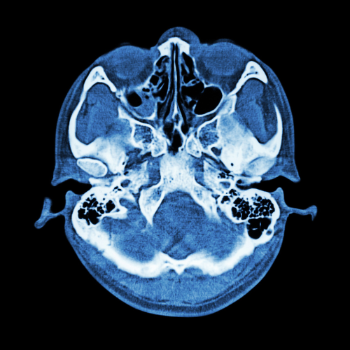

After a visit to Dr. Rajat, a renowned neurologist, and a series of diagnostic tests, Meera was diagnosed with a complex skull base tumor. This news was devastating, not only because of the potential threat to her health but also due to the intricate nature of the required surgery. Skull base tumors reside in a delicate area where the brain meets the spinal cord, surrounded by vital nerves and blood vessels. The very thought of surgery in such a sensitive region was daunting.

At this juncture, Meera's story intersects with the revolutionary world of skull base surgery. This advanced medical procedure is designed to address conditions like Meera's, offering a beacon of hope where traditional methods fall short. The procedure's primary goal is to remove tumors or abnormalities with precision, minimizing damage to surrounding structures.

The surgery was scheduled, and with meticulous planning and cutting-edge technology, Dr. Aryan and his team embarked on the delicate task of removing the tumor. The use of advanced imaging techniques and minimally invasive surgical tools ensured precision, reducing recovery time significantly.